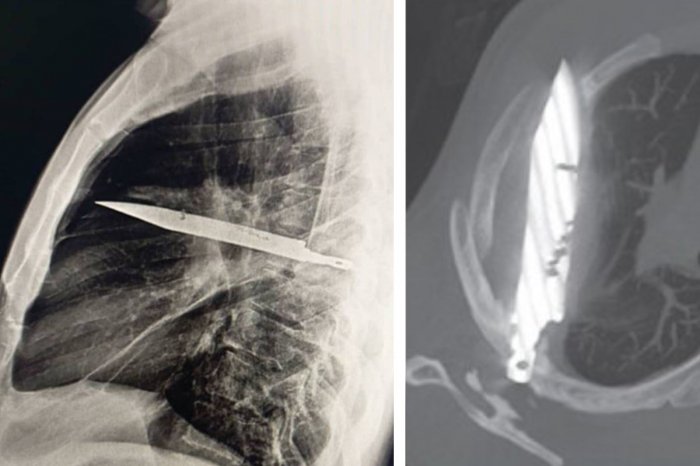

Muž prišiel na röntgen. Vyšetrenie odhalilo, že mal osem rokov v hrudníku zabodnutý nôž.

Ako informuje Dnevnik, muža preto radšej poslali na röntgen hrudníka. Keď lekári videl snímku, ostali nemo hľadieť.

V hrudníku muža sa nachádzal „ostrý kovový predmet“. Ako sa ukázalo, išlo o zlomený nôž obklopený hnisom a tkanivom! Zistili, že nôž vnikol do tela cez pravé rameno. Za to, že sa na to prišlo aj po rokoch, môže fakt, že muž žil ďaleko od nemocnice a nikdy v živote nepodstúpil röntgen.